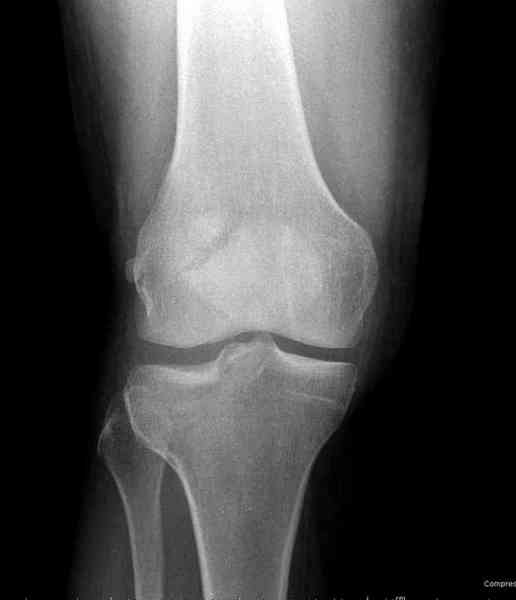

Как всегда прекрасная презентация. Совершенно согласен с необходимостью сохранять мениск и вообще согласен со всем, кроме одного. Фиксация должна проводиться после правильно выполненной репозиции. Главная цель репозиции - это восстановить высоту наружного мыщелка. В норме наружный мыщелок выше внутреннего на 4-5 мм на снимке в переднее заднем направлении АР.

Необходимость репозиции возникает при снижении высоты от 3 до 5 мм по разным источникам. По моему опыту 4 мм. Если не восстановить высоту мыщелка возникает вальгизация коленного сустава с относительным расслаблением передней крестообразной связки. При этом развивается нестабильность коленного сустава из-за недостаточности ПКС.

По этому если фрагмент большой есть необходимость репозиции дистального угла и фиксация пластинкой против соскальзывания ANTIGLIDING PLATE. Если перелом фрагментарный? то очень помогают описанные субхондральные шурупы RAFT, но

чтобы сохранить высоту суставной площадки шурупы одним концом должны опираться на пластинку а другим - на кортекс по внутренней стороне. Идеально сочетание ANTIGLIDING BUTRESS PLATE + RAFT SCREWS.

На представленном после операционном снимке нет репозиции, на что указывает низкое положение тибиального плато и перекрытие кортикальных пластинок в метафизарной части - указано стрелкой. Обычно чрескожную фиксацию я применяю

Мыщелок левой б/б кости репонирован закрыто, на контрольной рентгенограмме репозиция удовлетворительная, фиксировано спицами. гипсовая повязка.